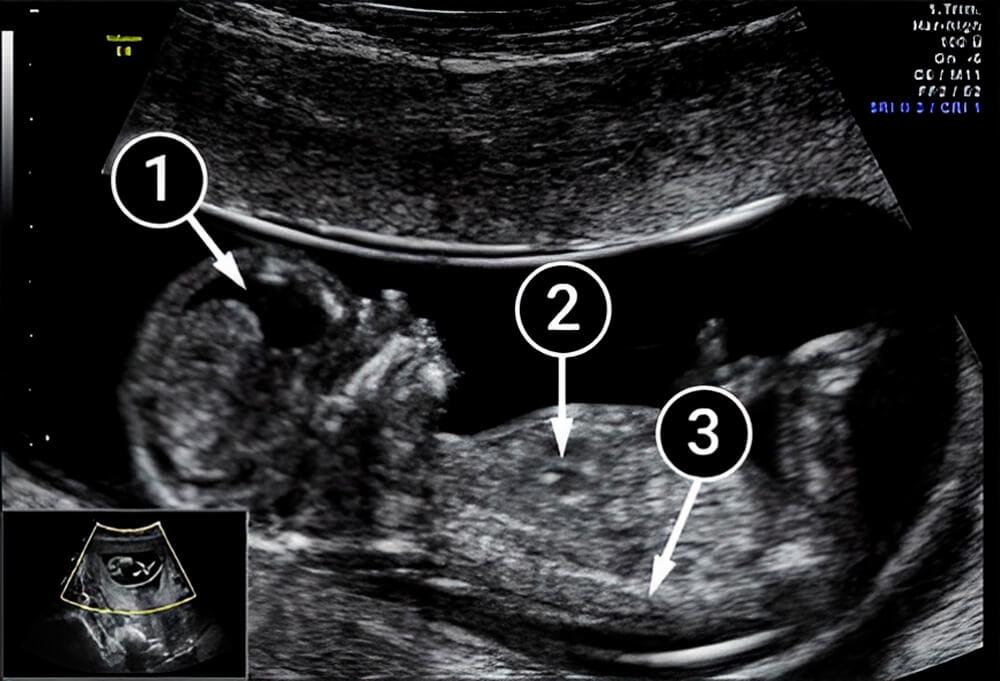

La siguiente imagen muestra bastante bien la cabeza del bebé. Una proyección clara de la cara permite ver las cuencas de los ojos debajo de los párpados, así como la nariz, la mejilla, el mentón e, incluso, el cuello del bebé.

La cabeza está levantada y el brazo derecho se encuentra a lo largo del torso. Su longitud es impresionante, pero esto es temporal, ya que las extremidades inferiores pronto alcanzarán a las superiores.

De igual forma, ya se ve un pequeño corazón en el tórax.

el cerebro

corazón

mano